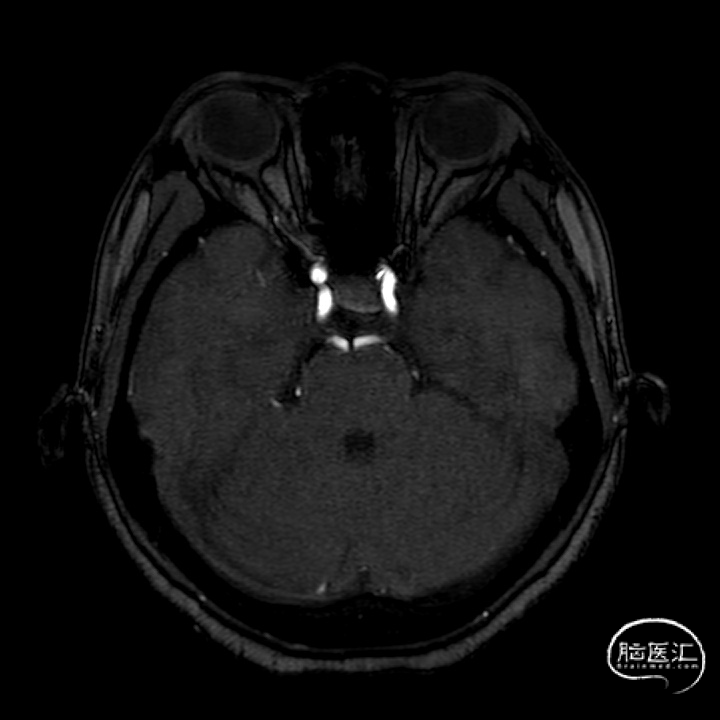

(A)

(B)

(C)

(D)

(E)

(F)

A:准备定位后打开Surpass Streamline头端于Catalyst 5。

B:缓慢回撤Catalyst 5,逐渐释放Surpass Streamline。

C:支架收尾。

D:Catalyst 5中间导管进行支架内按摩。

E:动脉瘤腔内可见造影剂滞留。

F:动脉瘤腔内可见造影剂滞留(另一角度)。